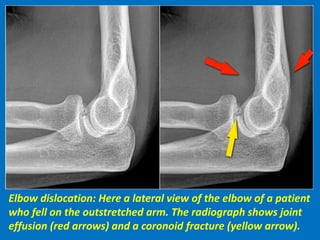

Elbow dislocation: Here a lateral view of the elbow of a patient

who fell on the outstretched arm. The radiograph shows joint

effusion (red arrows) and a coronoid fracture (yellow arrow).

Coronal view: Lateral collateral ligament is completely stripped (yellow arrow).

radial head is subluxed. marrow edema of the coronoid process due to the

fracture (red arrow).

Sagittal view: Radial head is a little bit subluxed posteriorly (yellow arrow).

Large effusion and capsular disruption posteriorly. Contusion of the posterior side

of the capitellum as a result of impaction by the coronoid process (red arrow).

Posterior elbow dislocation with contusion in the anterior side of the

radial head (red arrow) and on the posterior side of the capitellum.